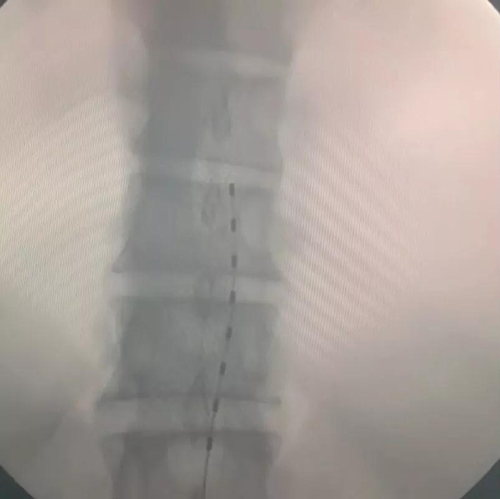

在排除了手术禁忌后,孙涛主任团队顺利完成了手术,术后当晚,张大爷露出了久违的笑脸。“我的脚不疼了”,他说:“有点麻麻的,过电的感觉,很舒服。”随后两天,张大爷下床活动,感慨终于不用跛脚走路了。如今他还在住院需要进一步的观察和电刺激参数的调整。

据悉,脊髓电刺激是一种侵入性的镇痛技术。通过植入设备发送弱电脉冲,刺激脊髓背侧特定节段,在脊髓水平,将外周感觉神经传入的痛觉以一种可以忍受的酥麻感替代,从而阻断痛觉上传到大脑中枢,达到缓解疼痛的效果。适用于脊髓电刺激的疾病有:顽固性腰腿痛或下背痛;复杂性区域疼痛综合征;带状疱疹性疼痛;难治性心绞痛;患肢/残肢痛;周围缺血性疼痛;慢性难治性心绞痛;脊髓损伤等。